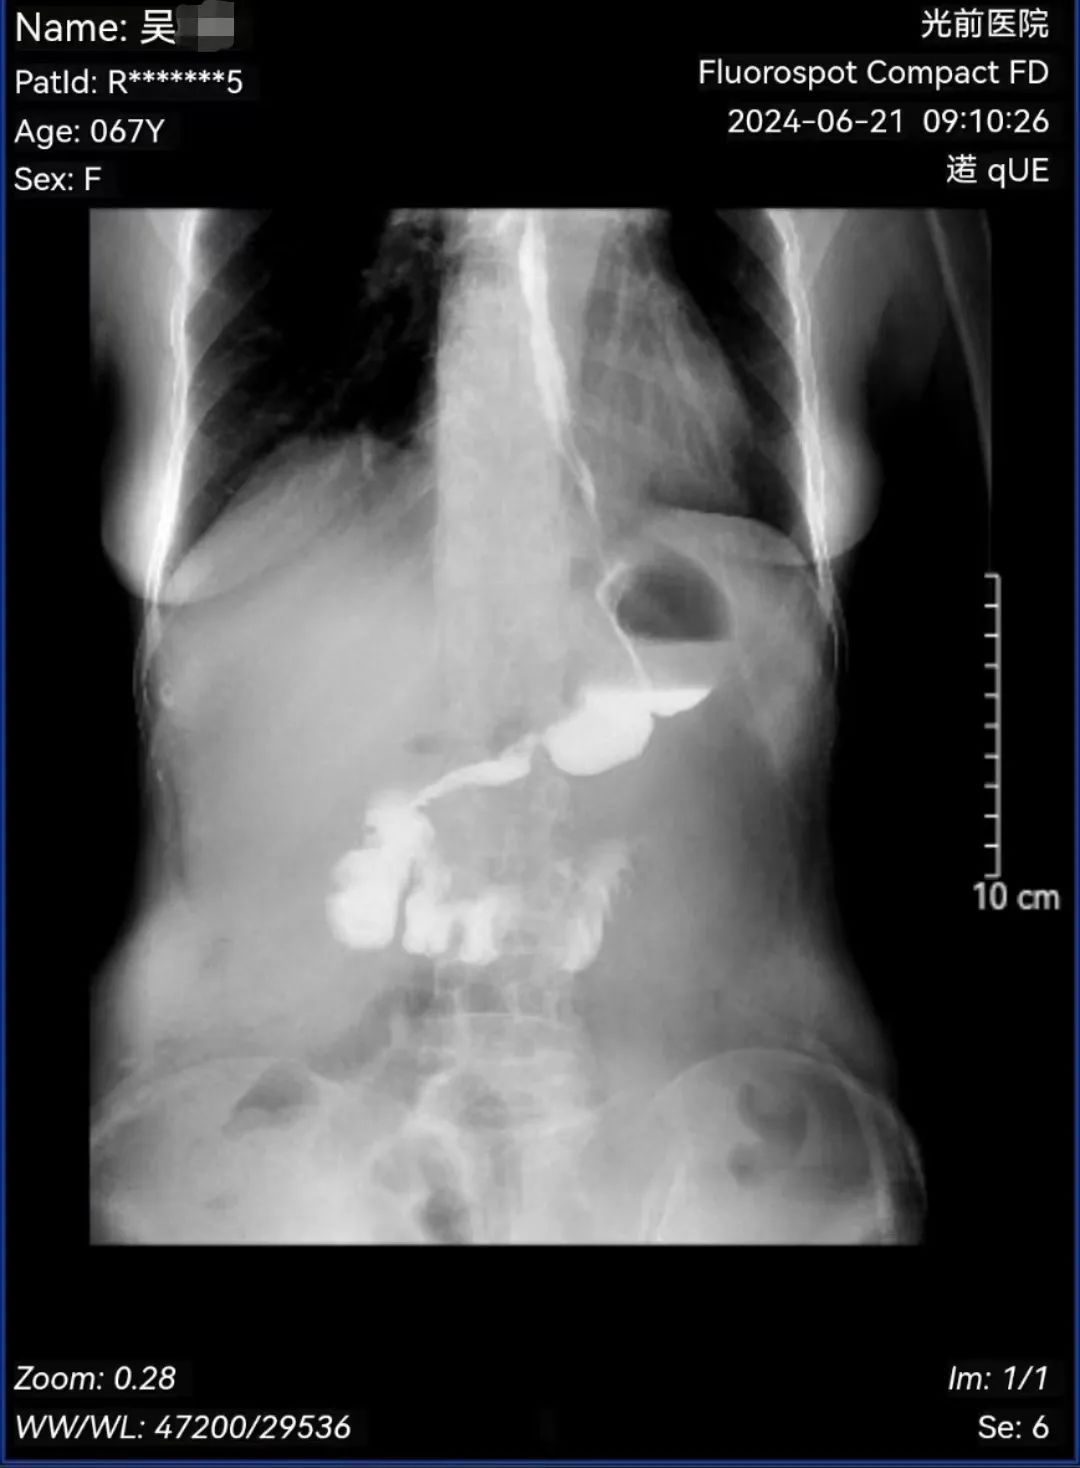

術(shù)后,在病區(qū)醫(yī)護(hù)團(tuán)隊(duì)的精心照料下,吳奶奶恢復(fù)快、進(jìn)食早、吞咽通暢、無明顯反流等不適,僅11天順利出院。

(術(shù)后第七天消化道造影)